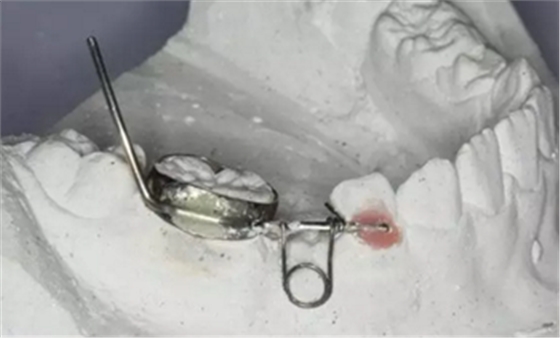

35、放回模型試合

36、放回模型試合,合面觀

37、放回模型試合,頰面觀

38、取下帶環(huán)、推簧加力

39、推簧加力后合面觀

40、加力后,重新就位合面觀

41、加力就位后測力值200~250克,初級力值偏大,隨著力的衰減力值維持在100~150g左右,直至間隙推開后,力值逐漸遞減為零,作為間隙保持器使用,等待恒牙萌出